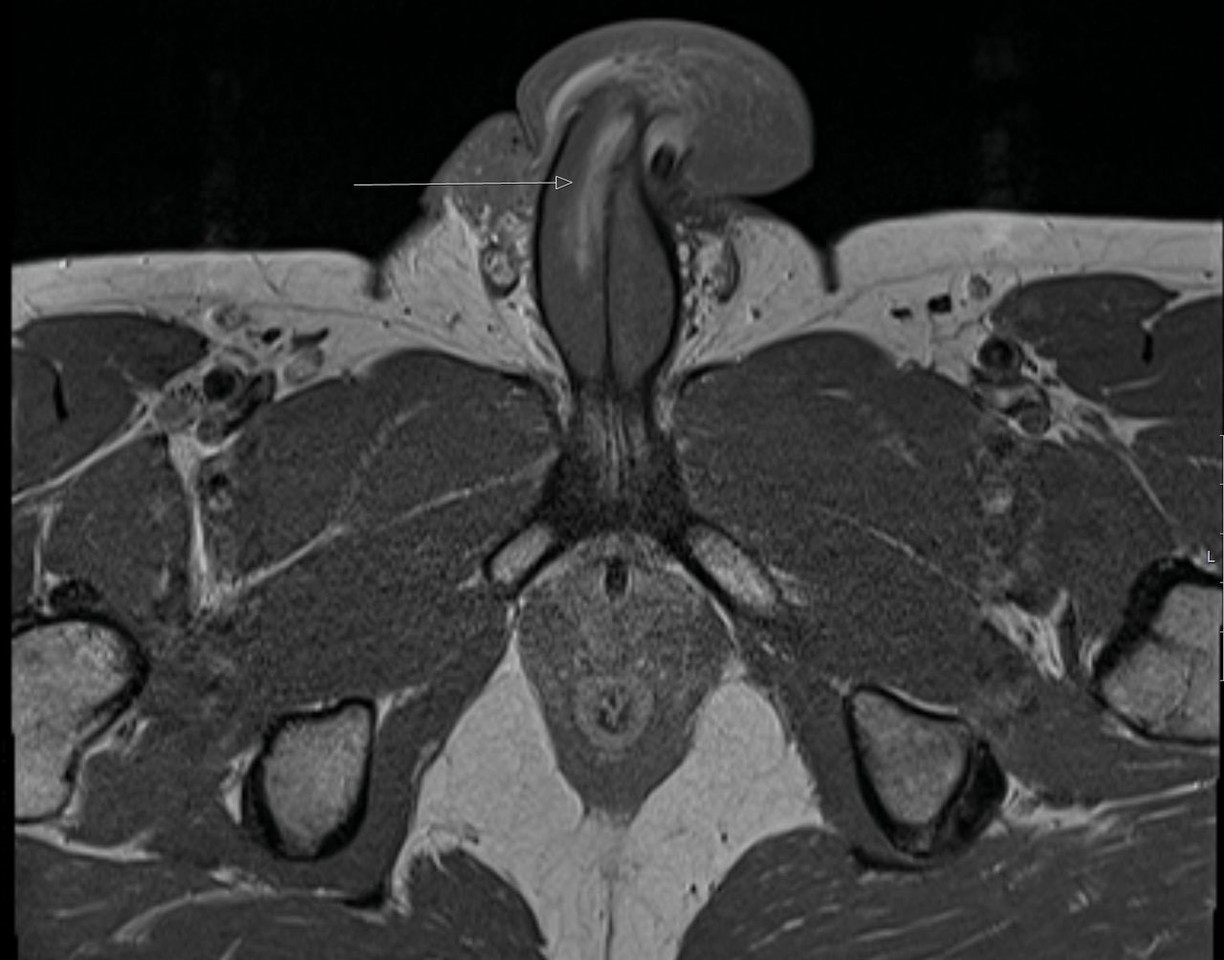

▲依據MRI掃描,醫師發現患者陰莖右側有一處3公分長的垂直受傷處。(圖/翻攝自《英國醫學期刊》)

綜合每日郵報等英媒報導,該名男子當時下體撞向伴侶的會陰處,也就是肛門與生殖器之間的位置,導致陰莖逐漸腫脹,呈現垂直骨折。依據MRI掃描,醫師發現患者的陰莖右側有一處3公分長的垂直受傷處。現已知他就醫後的手術相當成功,並於受傷6個月後恢復正常性行為,且術後陰莖勃起的狀況與受傷前相同,沒有陰莖彎曲或出現明顯疤痕。